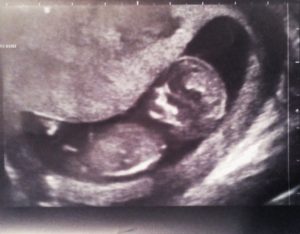

Тонус матки определяется по результатам ультразвукового исследования. УЗИ показывает изменение формы плодного яйца. Причины преждевременного сокращения бывают разные. Это и разного рода заболевания, обычно связанные с эндокринной системой, а также болезнями матки: эндометриоз, миома, цервикальная недостаточность. Данный недуг может быть также генетически обусловлен.

Способом медицинской диагностики гипертонуса может быть несколько. Прежде всего, это гинекологический осмотр с прощупыванием матки, а также проведение ультразвукового обследования с выявлением тонуса.

По данным УЗИ выявляется состояние тонуса стенок матки, особенно по отдельным ее стенкам и по степени выраженности. Это важно знать особенно в ранние сроки беременности, так как плод крепится к стенкам матки и от их состояния зависит его питание.